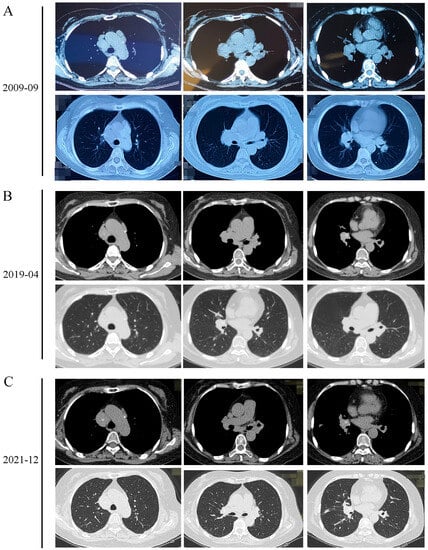

A 68-year-old woman was admitted with a 12-year history of enlargement of the intrathoracic lymph nodes and a 2-year history of shortness of breath. In 2009, enlargement of her intrathoracic lymph nodes was determined by chest computed tomography (CT) and physical examination (Figure 1A); however, she did not receive any treatment due to a lack of symptoms. In 2019, the patient experienced progressive shortness of breath during physical activities; this was occasionally accompanied by chest pain. The CT scan performed in 2019 demonstrated a new calcification of mediastinal lymph nodes, and the reduced size of lymph nodes compared with the previous examination (Figure 1B). The patient received intermittent oral administration of Andrographis Paniculate and the inhalation of corticosteroids when the shortness of breath worsened. She was admitted to hospital in December 2021 due to the exacerbation of breath shortness and underwent a chest CT scan, which indicated an enlargement of the intrathoracic lymph nodes with scattered calcification and a new opacity in the right middle lobe of the lung (Figure 1C). The patient had undergone appendectomy 30 years earlier and had a history of coronary heart disease for more than 10 years without being fully examined and treated. Laboratory test results are shown in Table 1. The patient had normal pulmonary function (forced vital capacity (FVC)%: 100.2%, forced expiratory volume in one second (FEV1)%: 92.5% and FEV1/FVC: 76.69%). The results of echocardiography indicated normal systolic function of the left ventricle (ejection fraction: 62%) and degeneration of the aortic valve. Ultrasound examination received fatty liver and lymph nodes in the neck, subclavian, armpit and groin.

Figure 1.

(A) The enlargement of intrathoracic lymph nodes was detected by chest CT scans in 19 September 2009. (B) 3 April 2019. (C) 2 December 2021. A new calcification of the mediastinal lymph nodes and a new opacity in the right middle lobe of the lung appeared in 3 April 2019 and 2 December 2021.